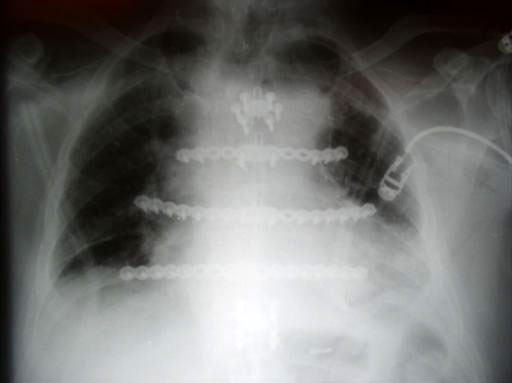

The Sternal Fixation System consists of titanium locking plates that function with 3.0 mm titanium locking screws, similar to those used in the mandible area. The straight plates are actually an assembly of two single plates, which are connected by a U shaped pin. In case of emergency removing the pin allows re-entry into the thoracic cavity. Long and straight plates are fixed to the ribs; additional smaller plates are available for fixation of the manubrium.

The Sternal Fixation System is available with 12-hole Titanium Locking Plates (Fig 2) as well as Titanium Locking H plates small/large and Titanium Locking Star Plates with 6 and 12 holes (Fig 3). The set contains Locking Screws (3.0 mm) from 8 mm to 18 mm and the Titanium Emergency Release Pin to connect and disconnect the plates at the fixation site,

A Titanium Sternal Locking Plate with 30 holes is available additionally (Fig 2).

Sternal closure with Ti Plate system

Cases provided by J Thornton, UT Southwestern Medical Center, Dallas, TX